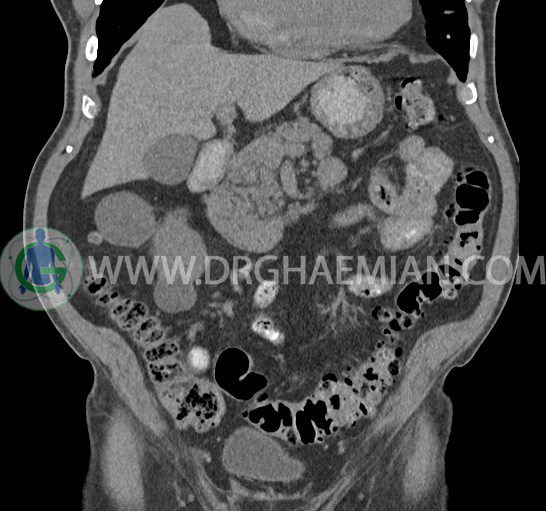

سی تی اسکن لگن یکی از روش های تصویربرداری با سی تی اسکن است. این روش با استفاده از تشعشعات تصاویر عرضی از ناحیه شکمی ایجاد میکند. در این کیس ديورتيكولوزيس، کیست های کورتیکال در هر دو کلیه، لنفادنوپاتی، کلسیفیکاسیون دیواره آئورت و شریان ایلیاک، تغییرات DJD ناحیه توراکولومبار و پروستات بزرگتر از عادی دیده می شود.

در سي تي اسکن اسپيرال شکم و لگن با و بدون کنتراست خوراکی و وريدی (مولتي ديدکتور 16 با مقاطع ظريف و بازسازي هاي ساژيتال و کرونال):

– کيست هاي کورتيکال ساده به قطر 5 mm تا 50 mm در کليه راست و به قطر 5mm تا 55 mm در کليه چپ

– توده ايزودنس به ابعاد mm 17 x 28 در پره ائورت مجاور قسمت تحتاني D3 دئودنوم مطرح کننده لنفادنوپاتي و با احتمال کمتر آنوريسم ترومبوزه (نيازمند مطابقت سونولوژيک)

– کلسيفيکاسيون ديواره آئورت و شريان ها ايلياک همراه با نشانه هاي ترومبوز مورال در بيفورکاسيون ائورت با امتداد به پروگزيمال هاي شريان هاي ايلياک

– ديورتيكولوزيس در کولون نزولي وسيگموئيد

لنفادنوپاتي به ابعاد mm 22 x 25 مجاور شريان ايلياک خارجي چپ و به ابعاد mm 17 x 28 مجاور شريان ايلياک خارجي راست

– تغييرات DJD در ناحيه توراکولومبار و

– پروستات به ابعاد mm 45 x 54، بزرگ تر از نرمال

مشهود است.